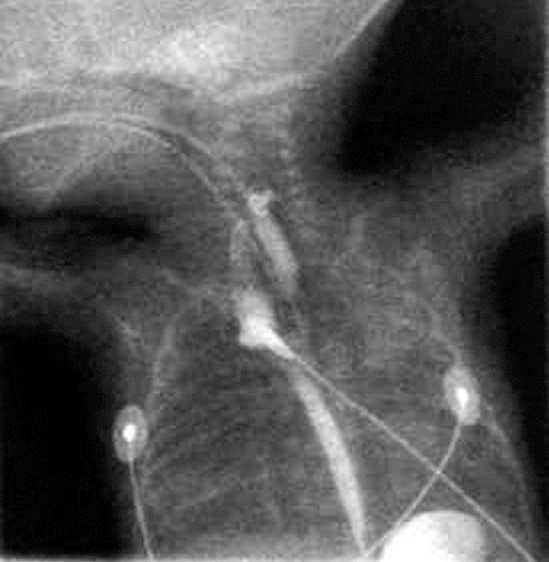

En los días siguientes, el cuadro respiratorio empeoró, apareció un enfisema subcutáneo con aparición de un enfisema intersticial en la radiografía de tórax (fig. 1), y se instauró ventilación de alta frecuencia. Posteriormente, pudo pasar de nuevo a VMC, y fue extubado 24 h después, aplicándose presión positiva continua en la vía aérea por vía nasal (n-CPAP). El neumomediastino persistió sin neumotórax asociado.

Figura 1. Radiografía de tórax y abdomen. Se observa la existencia de un neumomediastino con enfisema intersticial y enfisema subcutáneo en la faringe.